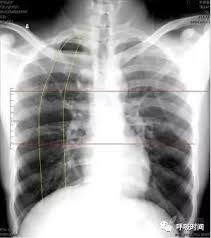

胸片,即胸部x光片,是医学上常用的一种检查手段,主要用于观察肺部、心脏、肋骨等胸部结构的异常情况。胸片曝光是指通过x射线对胸部进行照射,并将影像记录在胶片或数字探测器上的过程。这一过程的目的是为了辅助医生进行疾病诊断,而非满足个人好奇心或娱乐需求。

在获取胸片曝光信息后,患者应保持理性态度,正确解读胸片结果。胸片上的影像信息需要由专业医生进行解读和分析,患者不应自行判断或解读胸片结果,以免因误解或误判而引发不必要的恐慌或焦虑。如果对胸片结果有疑问或担忧,应及时向医生咨询并寻求专业建议。